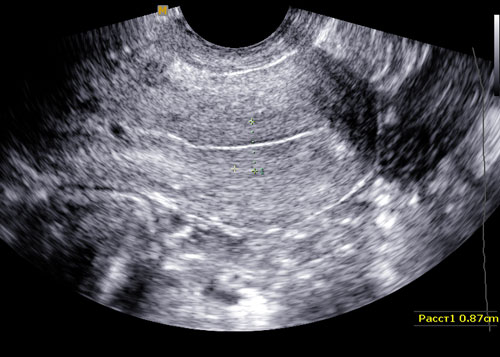

- УЗИ органов малого таза;

По УЗИ несложно определить существуют ли проблемы с детородным органом или причиной возникновения расширения стал ежемесячный период менструации. Но не только ультразвук прописывают пациенткам, при наличии показаний гинеколог может назначить КТ органа.

УЗИ матки и придатков поможет увидеть размеры органа, определить наличие отклонений и патологий.